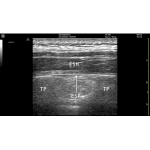

There are few effective strategies for the management of acute severe pain. Opioid analgesics can be effective but are associated with many negative effects, including respiratory suppression, sedation and dependence. Local anaesthetics are an attractive alternative. They prevent conduction of nerve fibres by blocking sodium channels on the cell membrane and reduce the transmission of […]